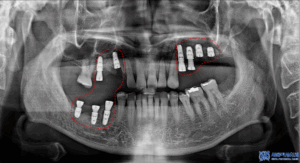

이후 발치 후 상악동거상술과

뼈이식을 동반한

무절개임플란트 수술을

진행하였습니다.

위, 아래 총 9개의

임플란트 식립이

이루어졌습니다.

또한, 잇몸뼈의 소실로 인해

뼈이식도 함께 진행하였습니다.

이를 통해 충분한 뼈량을 확보하고,

임플란트가 안정적으로

자리 잡을 수 있는

환경을 조성했습니다.